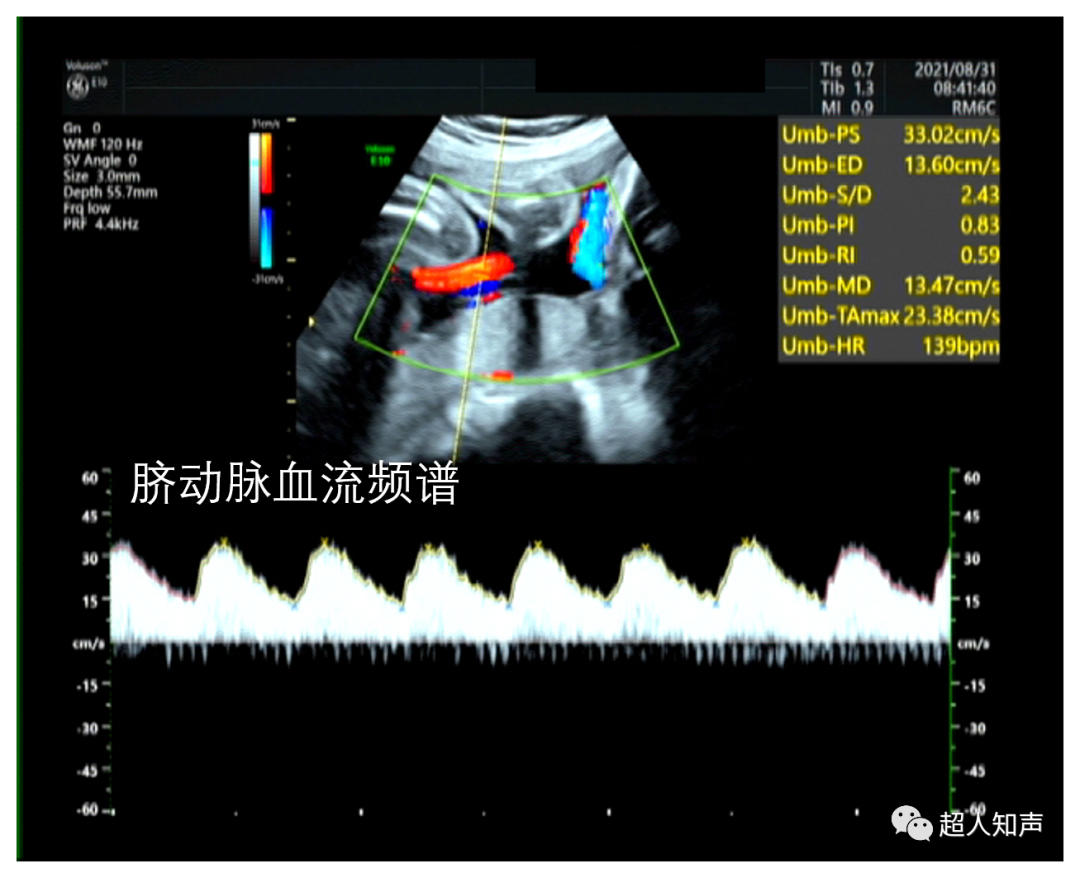

1.可直接测量出Vs和Vd。(如上图:PSV和EDV)

3.收缩舒张比值:S/D=Vs/Vd

4.舒张平均比值:D/M=Vd/Vm或收缩平均比值S/M=Vs/Vm

5.阻力指数RI=(Vs-Vd)/Vs

6.搏动指数PI=(Vs-Vd)/Vm

7.加速时间AT:频谱图从基线开始到波峰的时间,单位:ms

8.减速时间DT:从频谱图波形顶峰下降到基线的时间,单位:ms

9.测量跨瓣压差。可利用简化伯努利方程△P=4Vmax2计算,△P即压差(PG),Vmax为Vp,单位是m/s。(如下图:PG=4×1.142≈5mmHg)

同时,通过测量S/D、RI等参数可以帮助我们更好的鉴别肿块,例如:肝局灶性结节性增生(FNH)可测及动脉血流信号,RI多小于0.6;而肝癌可检测到动脉血流信号,RI>0.6。